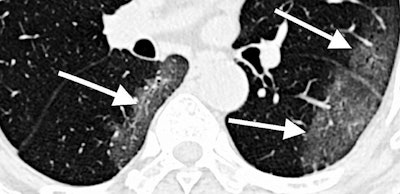

The MIDRC has published an initial set of anonymized images of COVID-19-positive chest CT scans and plans to include x-rays as well. The center seeks to have the largest open database of anonymized COVID-19 medical images, along with associated clinical data, in the world, the MIDRC said.

Freely available, the imaging data may be used for research, education, developing artificial intelligence (AI) software, deep-learning tools, and to serve as a general reference to clinically recognize COVID-19.

The RSNA led the charge surrounding COVID-19 images and released the initial set of such images through its RSNA International COVID-19 Open Radiology Database (RICORD). The society is currently processing additional contributions, and it has also partnered with the Society of Thoracic Radiology to source 120 CT scans from four international sites.